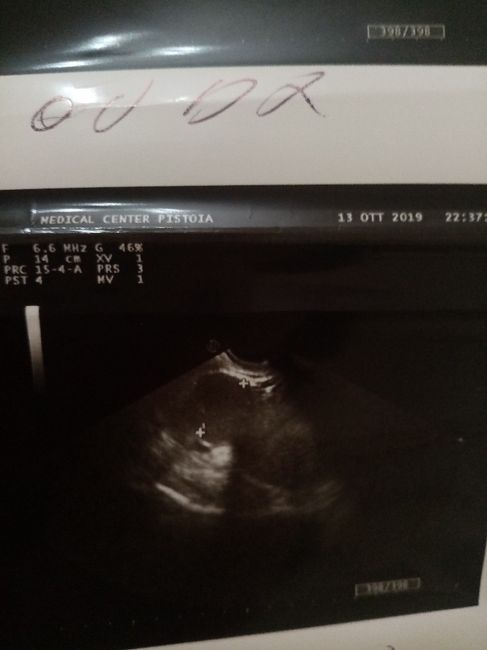

Ecco la mia

Non sò se potete aiuarmi... 2